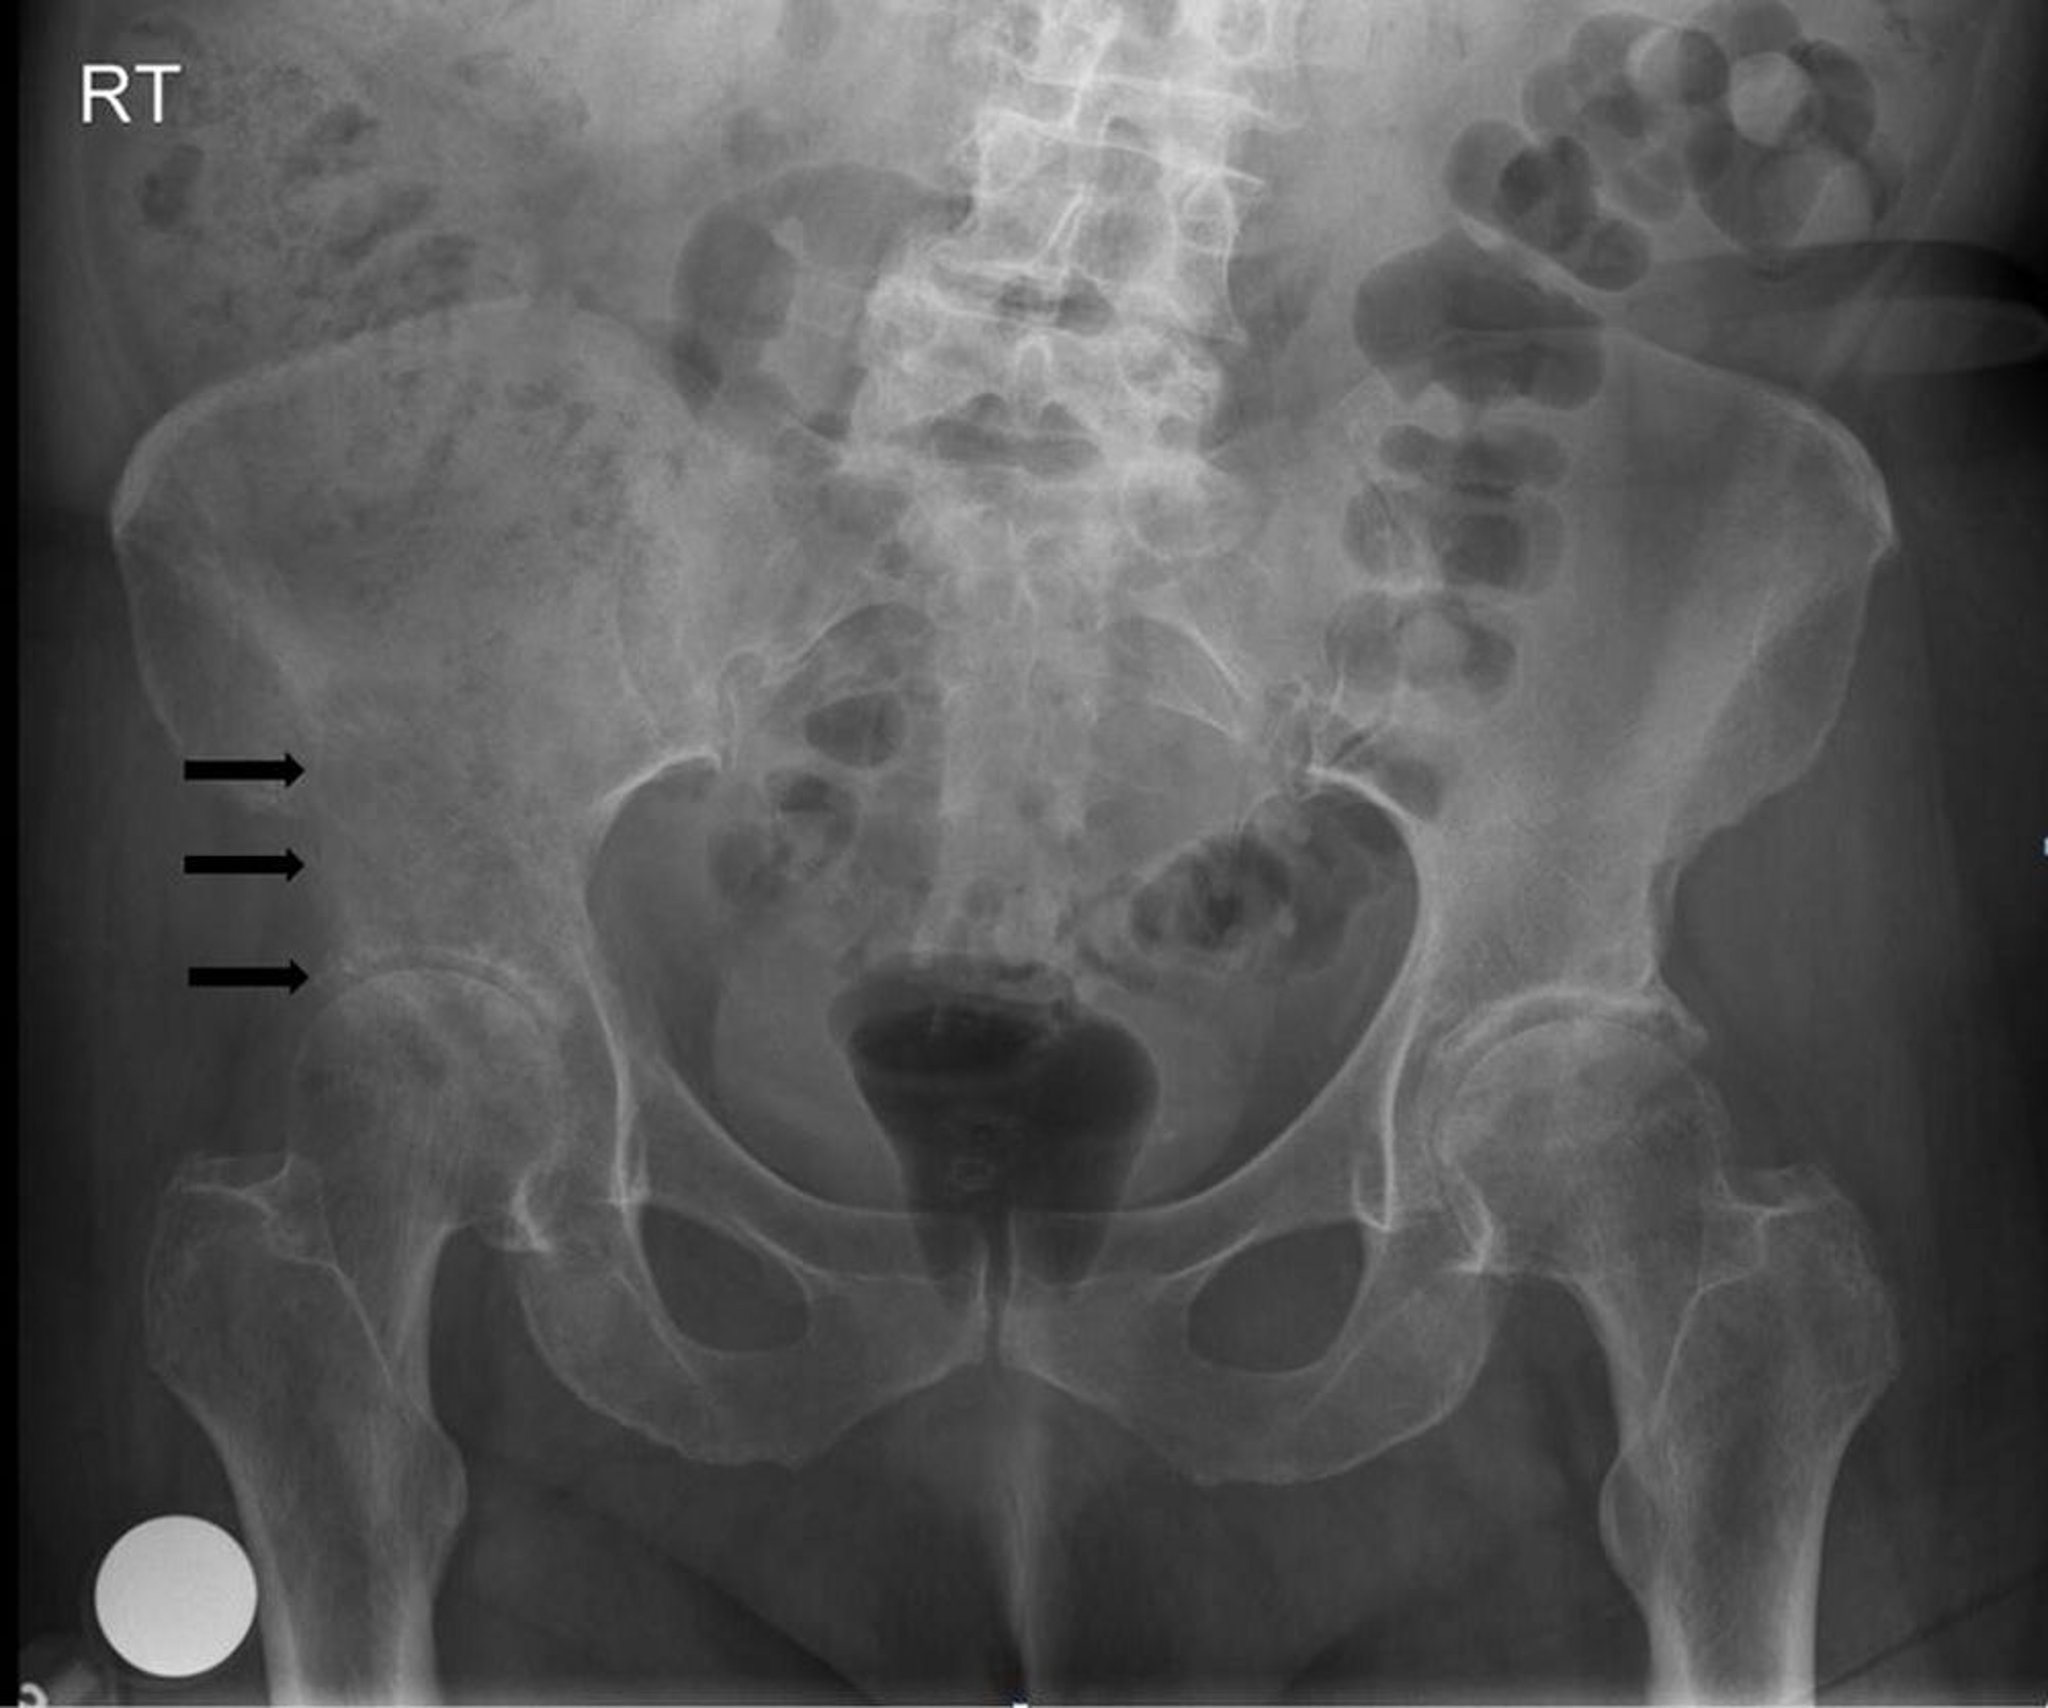

Phim chụp X-quang xương chậu này cho thấy tổn thương phá hủy, tiêu xương ở và phía trên ổ cối phải (mũi tên), phù hợp với di căn.

Hình ảnh do bác sĩ Michael J. Joyce, và bác sĩ Hakan Ilaslan cung cấp.